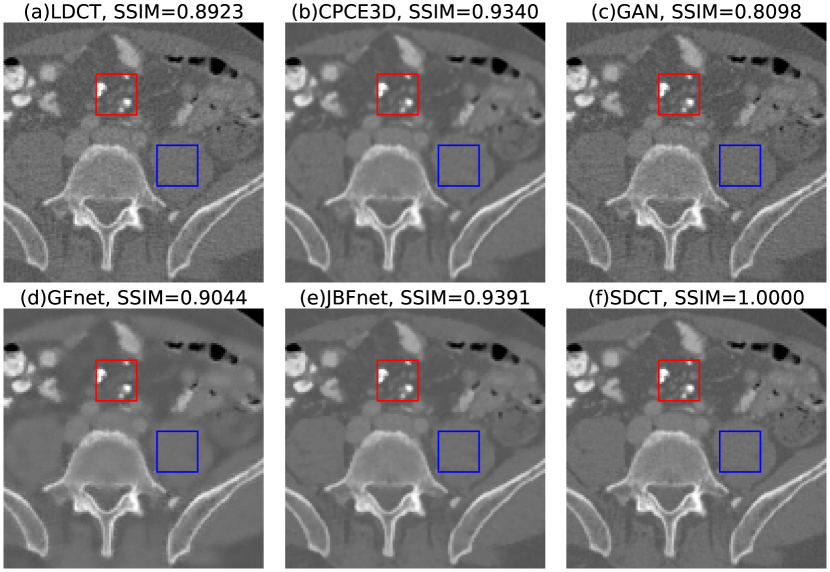

Refer to caption

Figure 3: We display an example of (a) low dose CT, denoised by (b) CPCE3D (c) GAN, (d) GFnet (e) JBFnet, and finally (f) the standard dose CT. The red square indicates some small low contrast features. The blue square indicates a homogenous noisy patch. SSIM scores are displayed in the captions. JBFnet achieves the best performance (SSIM = 0.9391). Images are displayed with a window of [-800, 1200].

3.2 Comparison to State-of-the-Art Methods

We compare the denoising performance of JBFnet to other denoising methods that use deep learning. We compare JBFnet against CPCE3D [20], GAN [23], and deep GFnet [24] (Fig. 3). All networks were trained over 30 epochs on the same dataset. JBFnet achieves significantly higher scores in both PSNR and SSIM compared to GAN and deep GFnet (w = 0.0, p = 0.005). CPCE3D achieves a significantly higher PSNR than JBFnet (w = 0.0, p = 0.005), but a significantly lower SSIM (w = 0.0, p = 0.005) (Table 1). Additionally, the JBF block consists of only 112 parameters, compared to the guided filtering block [24] which contains 1,555 parameters.